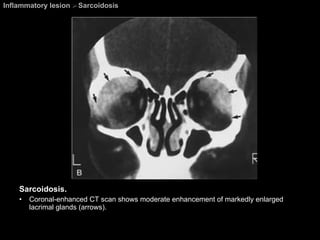

Sarcoidosis Ophthalmic lesions develop in approximately 25% of patients. Chest abnormalities are found in about 80% of patients with ocular sarcoidosis. Any part of the globe or orbit may be involved.  M/c orbital involvement  =  chronic dacryoadenitis .  May be unilateral and easily mimic a lacrimal gland tumor.

Sarcoidosis A Mikulicz-like syndrome  =  Sacoidosis involvement of bilateral lacrimal glands and salivary gland causings dry eyes and xerostomia. The most common cranial nerves to be affected are the  CN 2 , 7, 5, 8, 3, 6 respectively.

Inflammatory lesion  >  Sarcoidosis Sarcoidosis.  Coronal-enhanced CT scan shows moderate enhancement of markedly enlarged lacrimal glands (arrows).